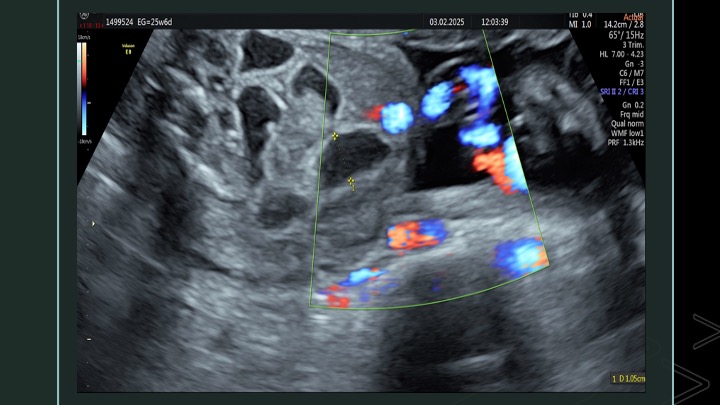

Se presenta el caso de una paciente de 23 años de edad, secundigesta, sin antecedentes personales ni familiares de relevancia. La paciente adjunta el estudio de screening de aneuploidías de la semana 11-14, que arroja bajo riesgo. Las imágenes 1 y 2 describen los hallazgos identificados durante la evaluación de la anatomía fetal en la semana 12. Las imágenes 3, 4 y 5 corresponden a los controles ecográficos posteriores, del segundo y tercer trimestre. La imagen 6 muestra al recién nacido. Seleccione la opción correcta: A. Corresponde a una hernia umbilical fisiológica con resolución más tardía. B. Corresponde a una gastrosquisis con cierre espontáneo intraútero. C. Corresponde a un onfalocele con ruptura del mismo. D. El defecto de pared cerró espontáneamente mejorando el pronóstico y riesgo de complicaciones gastrointestinales. Figura 1: se visualiza corte axial del abdomen fetal, a nivel de la inserción del cordón umbilical, con Doppler color en semana 12. Figura 2: se observa corte axial, a nivel de la inserción del cordón umbilical en la pared abdominal anterior, en semana 12. Figura 3: corte sagital a nivel de la inserción del cordón en la pared abdominal anterior, con Doppler color, en semana 20. Figura 4: corte axial del abdomen fetal, en semana 32, donde se identifica dilatación de las asas intestinales. Figura 5: corte axial del abdomen fetal, en semana 32, donde se identifica dilatación de las asas intestinales, con la utilización del Doppler color. Figura 6: se observa al recién nacido.

El caso presentado corresponde a una paciente de 23 años, secundigesta, sin antecedentes personales de relevancia, con embarazo único y espontáneo, que concurre al consultorio de ecografía para realizar un screening combinado del primer trimestre en la semana 12. Se evidencia solución de continuidad en la pared abdominal anterior, adyacente al cordón umbilical, con exteriorización de asas intestinales, compatible con gastrosquisis (Figuras 1 y 2).

A las 23 semanas de gestación, se realiza una evaluación anatómica completa donde no se pudo constatar la exteriorización de asas intestinales descrita en estudios previos. A nivel intra-abdominal, se evidenció en la región adyacente a la inserción del cordón, asas intestinales dilatadas, con pared ecogénica y engrosada, la mayor de 8,5 mm. Estos hallazgos fueron interpretados como intestino evanescente en contexto de gastrosquisis (Figura 3). El resto de la anatomía fetal impresionó conservada, con evaluación ecocardiográfica fetal normal en semana 25.